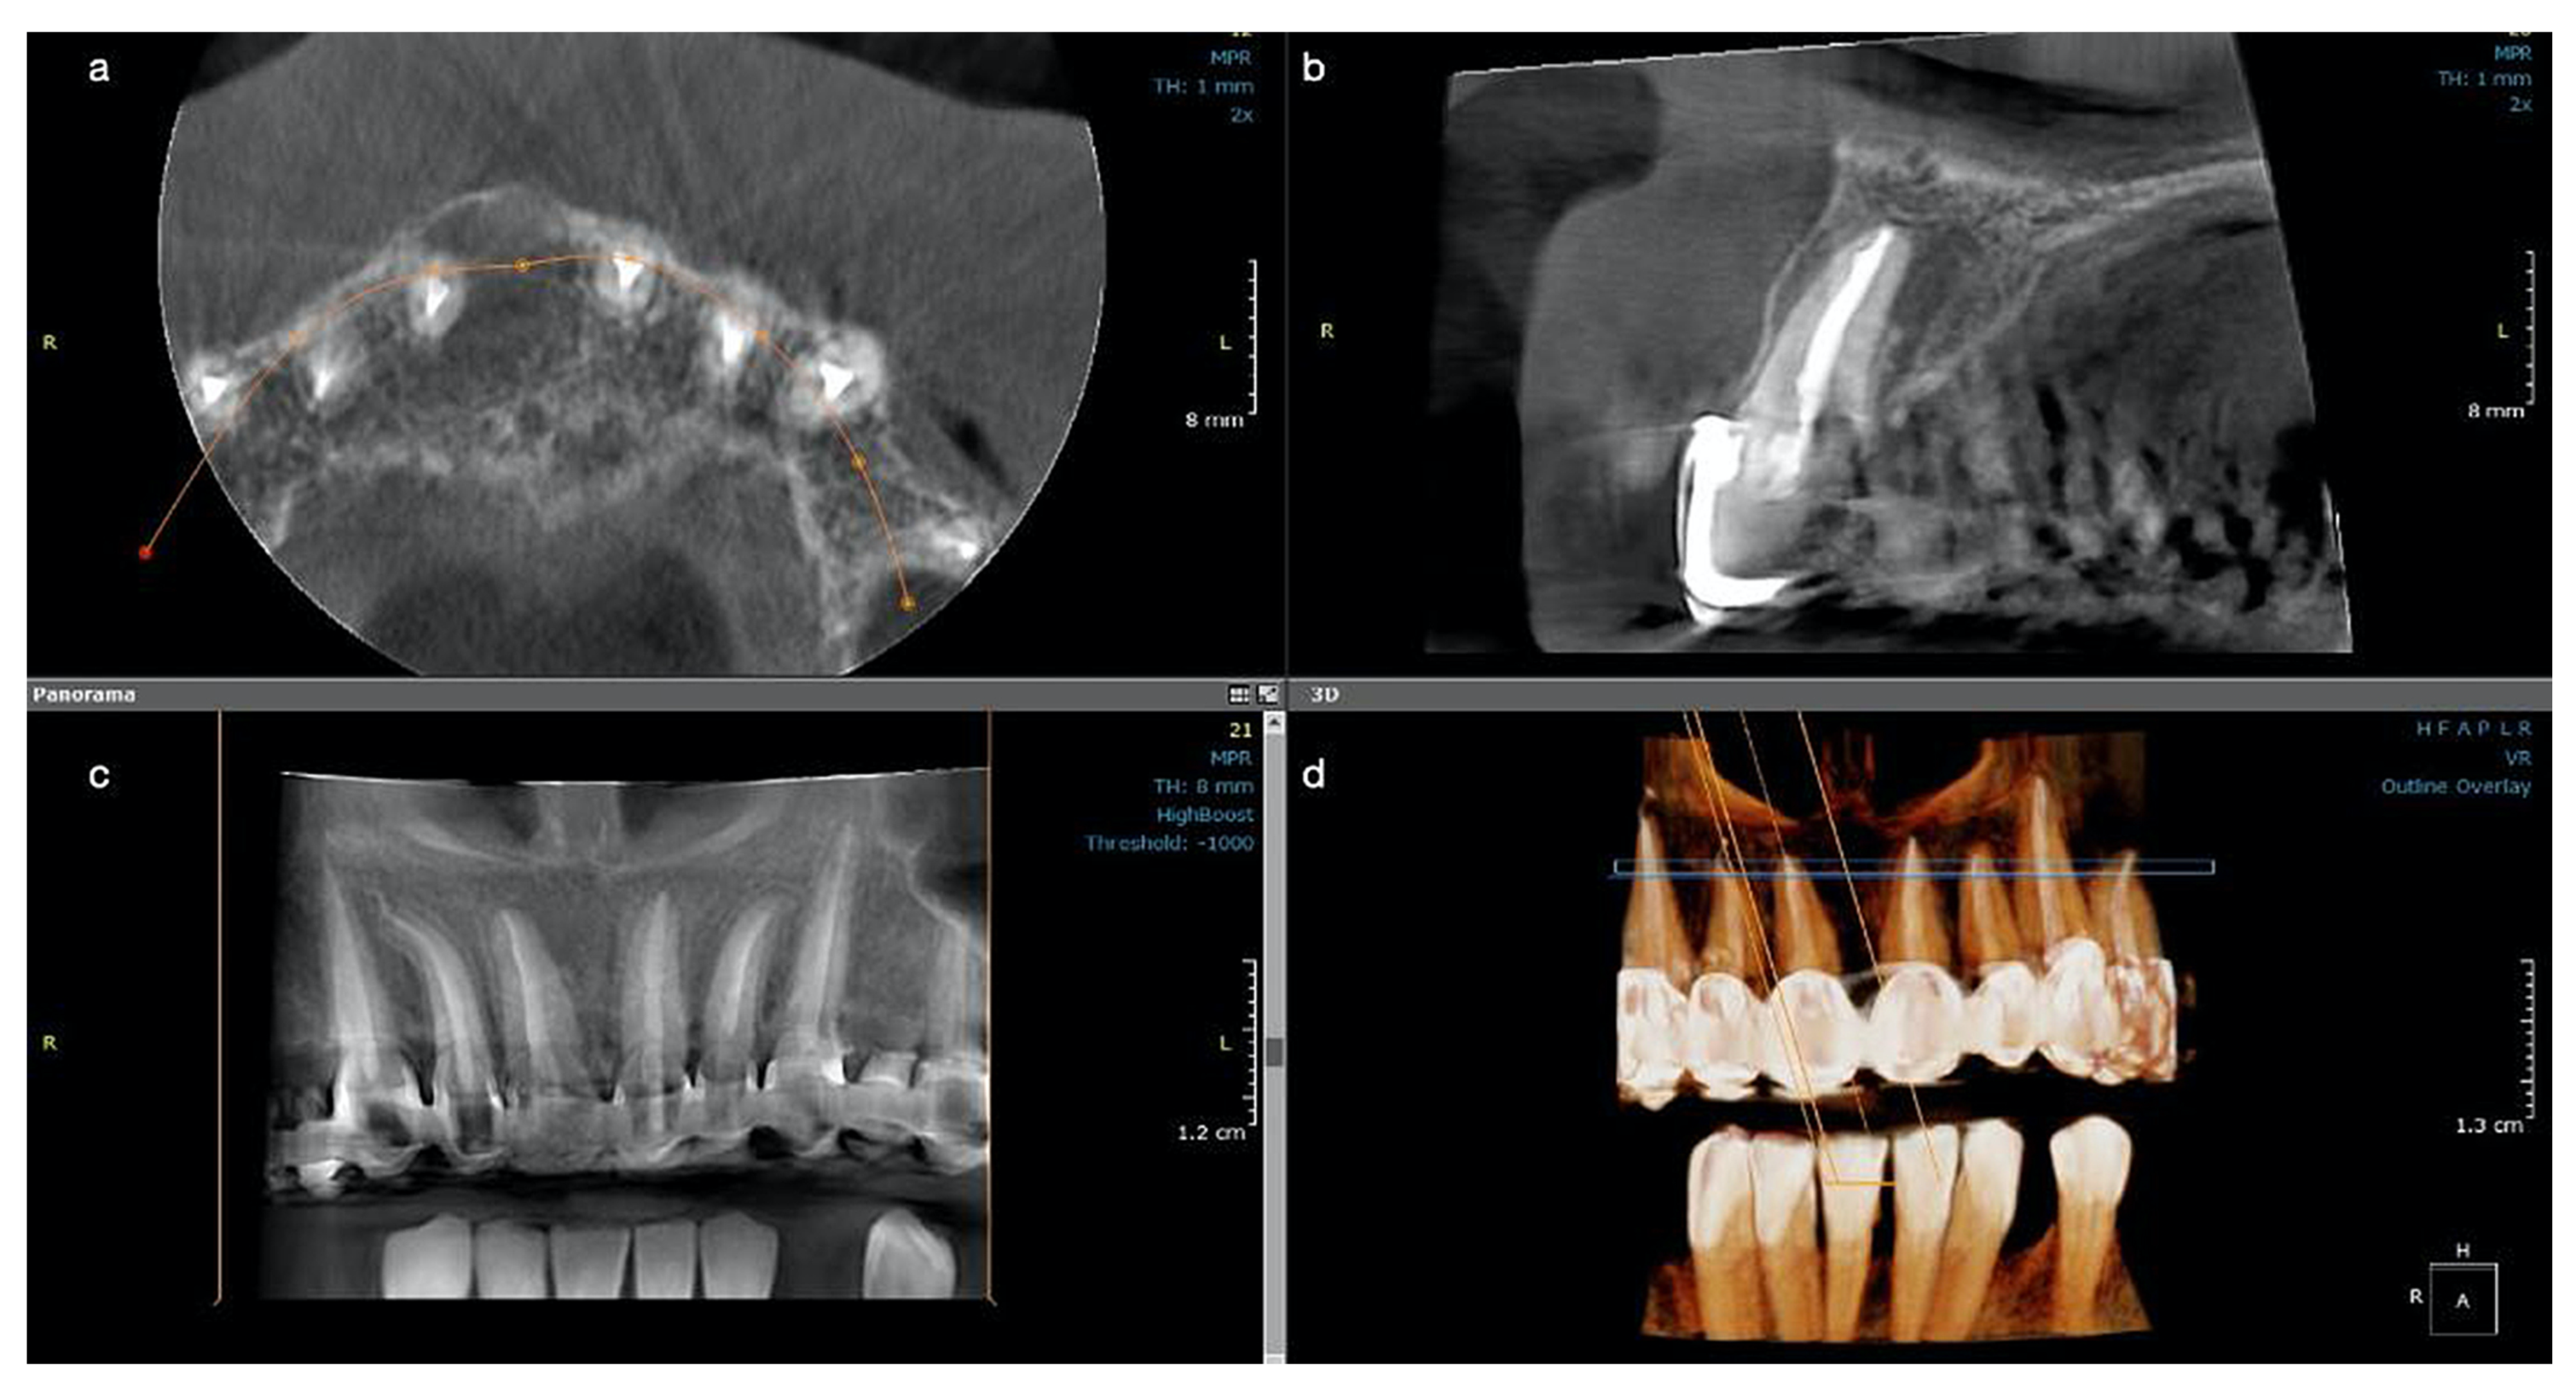

The postoperative CBCT scan at 12 months revealed the continuous formation of the bone, while the lesion continued to heal, remineralization was observed buccally around the entire root contour, and the palatal radiolucency was also decreased, with the observation of an increased bone regeneration activity and more trabeculae filling the lesion (Figure 3a–d). Both CBCT investigations performed at recall had the same characteristics: 5 × 5 cm field of view, 85 µm voxel size, 90 kV, 6.3 mA and 8.70 s emission, and were analyzed with the same program (OnDemand3D, KaVo Dental GmbH) on the same computer screen as the initial one. At present, the patient is still symptom-free and another clinical and radiological control will follow at 18 months.

Figure 3. Case 2. CBCT scan for tooth #11 at the one-year control: (a) The buccal cortical plate is completely restored, and new bone trabecula can be observed; (b) The lesion looks almost completely healed buccally and with a significant reduction in size palatal and height; (c) newly formed bone now occupies the cavity of the former lesion; (d) the 3D reconstruction shows the quality of the endodontic treatments on all upper frontal teeth.